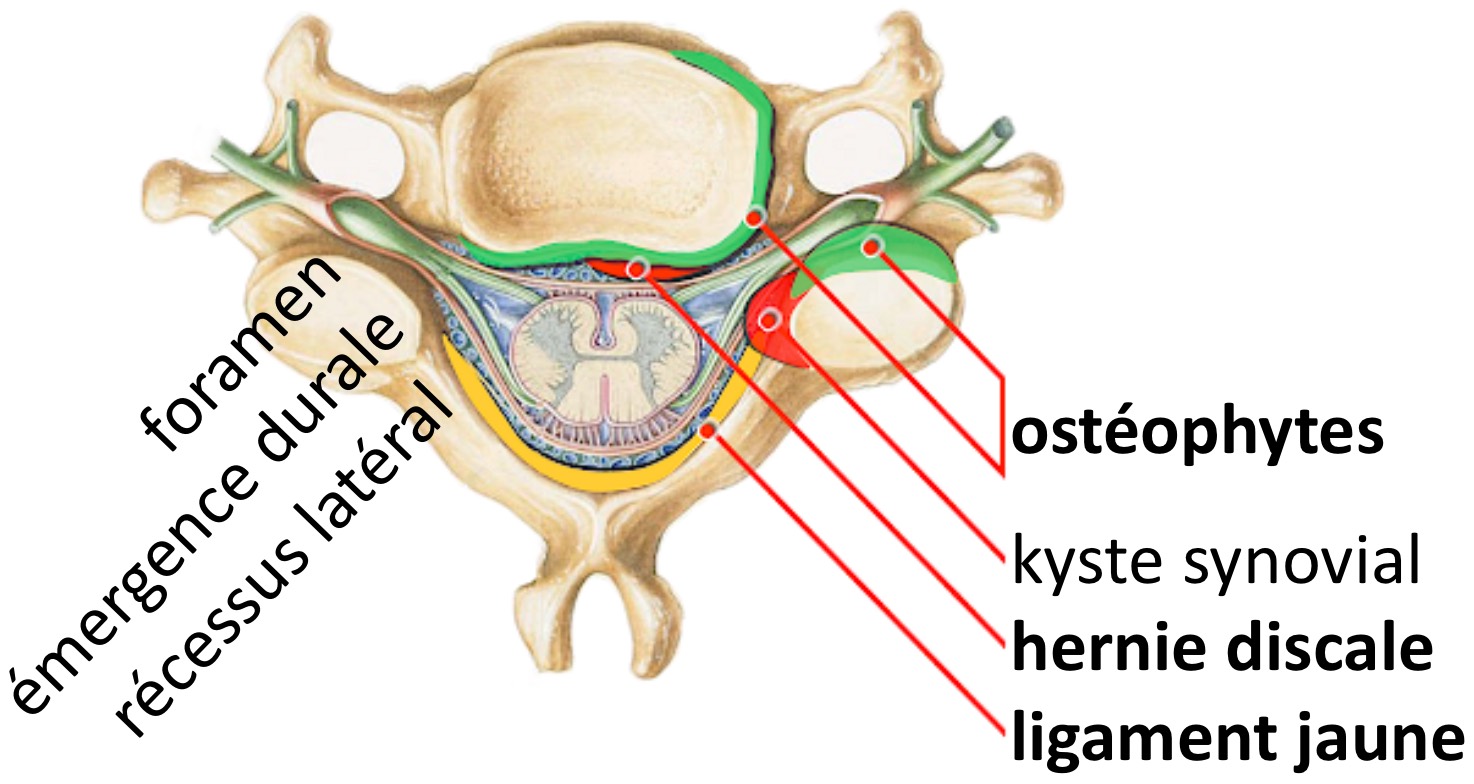

Arthrose zygapophysaire prédominant en sans œdème des berges articulaires.

En L4-L5 : Etalement discal global avec composante foraminale, sans rétrécissement canalaire ou foraminal significatif ni argument en faveur d’un conflit discoradiculaire.

En L5-S1 : Etalement discal global avec composante foraminale, sans rétrécissement canalaire ou foraminal significatif ni argument en faveur d’un conflit discoradiculaire.